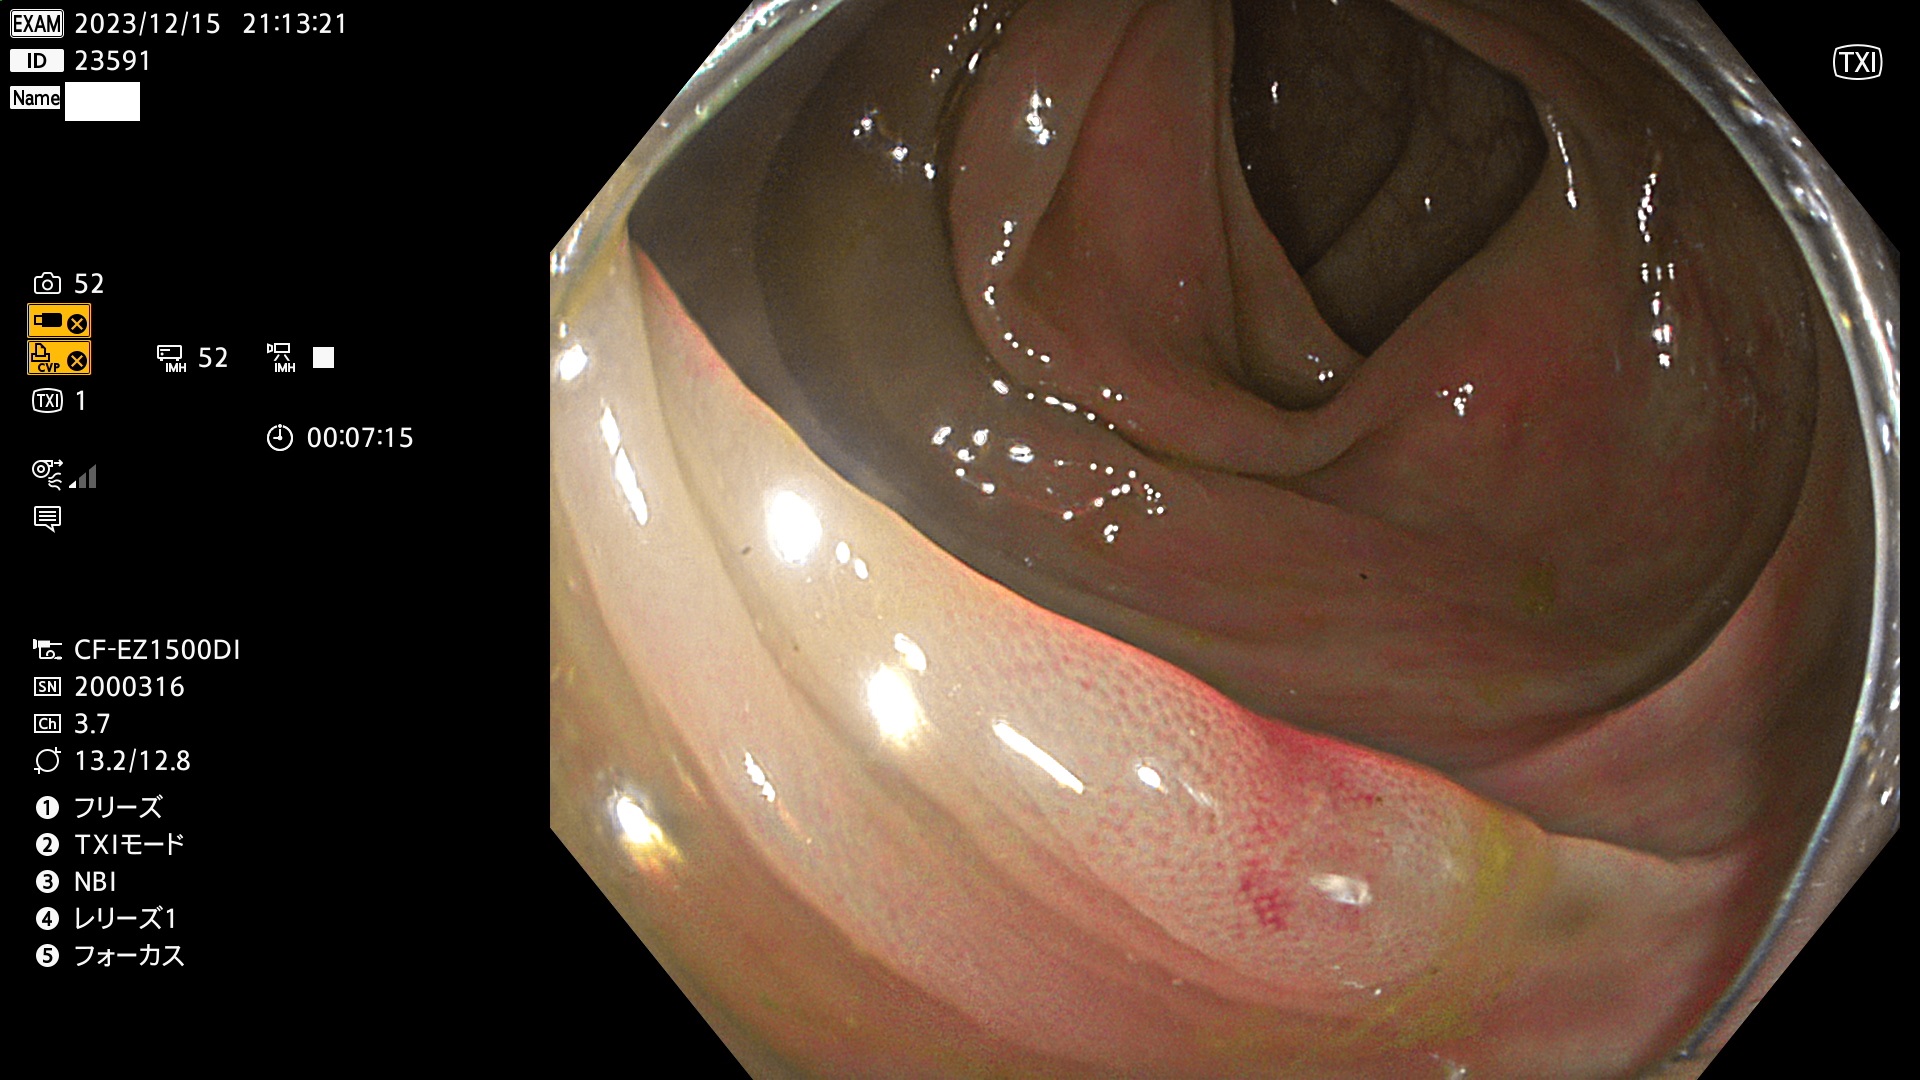

表面型腺腫(Flat Adenoma)の中で、完全に平坦な物をUb、陥凹している物をUcと呼びます。平坦隆起型(Ua)よりも、発見が難しく危険な病変です。このタイプは「内視鏡後・大腸癌の重要犯人」であり、この発見率は「腺腫発見率」よりも、重要な意味があります。

毎週の検査(木・金・土・日)に発見されたUb、Uc型・腺腫を、その週の日曜の夜にUPし1週間、提示します。

抽出の対象期間 2023年12月14日(木)〜12月18(日)の5日間(60件の検査)7件

当院で発見された炎症(ビラン)と紛らわしい腺腫